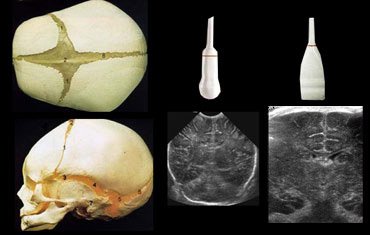

Нейросонографія (НСГ)

Такий метод дозволяє обстежити судинну систему немовлят до року. Дослідження голови роблять через джерельце, який ще не закритий. Застосовується при пологових травмах. Вивчається стан ликворопроводящей системи, параметри кровотоку. Спеціаліст дивиться, чи відповідає нормам розвиток мозку. Дослідження судин головного мозку має велике значення, так як вчасно виявлені дефекти дозволяють своєчасно провести терапію. Апаратура не викликає дискомфорт у дитини.